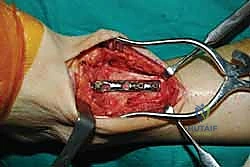

خطوات جراحة تثبيت مفصل الكاحل الأمامي بالتفصيل (Step-by-Step Surgical Procedure)

تُجرى العملية تحت التخدير العام أو النصفي (الشوكي)، وتستغرق عادةً بين ساعتين إلى ثلاث ساعات، وتتطلب دقة ومهارة فائقتين. إليكم الخطوات الجراحية كما ينفذها الأستاذ الدكتور محمد هطيف:

1. الوضعية والشق الجراحي (Positioning and Incision)

يستلقي المريض على ظهره (Supine position). يتم استخدام عاصبة (Tourniquet) حول الفخذ لتقليل النزيف وتوفير رؤية واضحة. يقوم الدكتور هطيف بإجراء شق طولي أمامي فوق مفصل الكاحل، عادة بين وتر العضلة الظنبوبية الأمامية (Tibialis Anterior) ووتر العضلة الباسطة الطويلة لإصبع القدم